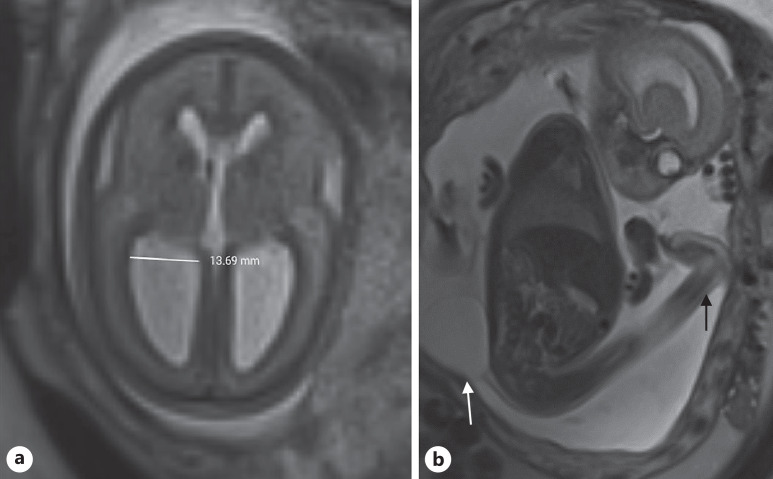

Results: This study included 71 fetuses with OSB for which 38 MRI examinations were analyzed; 61% (43/71) of lesions were MMC and 39% (28/71) were MS. Grade 3 (severe) Chiari II malformations were found in 80% (12/15) of MS and 43% (10/23) of MMC (p < 0.05). Fetuses with an atrial diameter less than 13.48 mm had a lower probability of requiring a CSF shunt at 12 months (p < 0.05). MMC was associated with a significantly higher frequency of clubfoot at birth (p < 0.05), whereas MS was significantly associated with more severe CHMII (p < 0.05). Although the correlations were not significant, we observed clear trends that more children with MS required shunts at 12 months and could walk at 30 months compared to children with MMC.